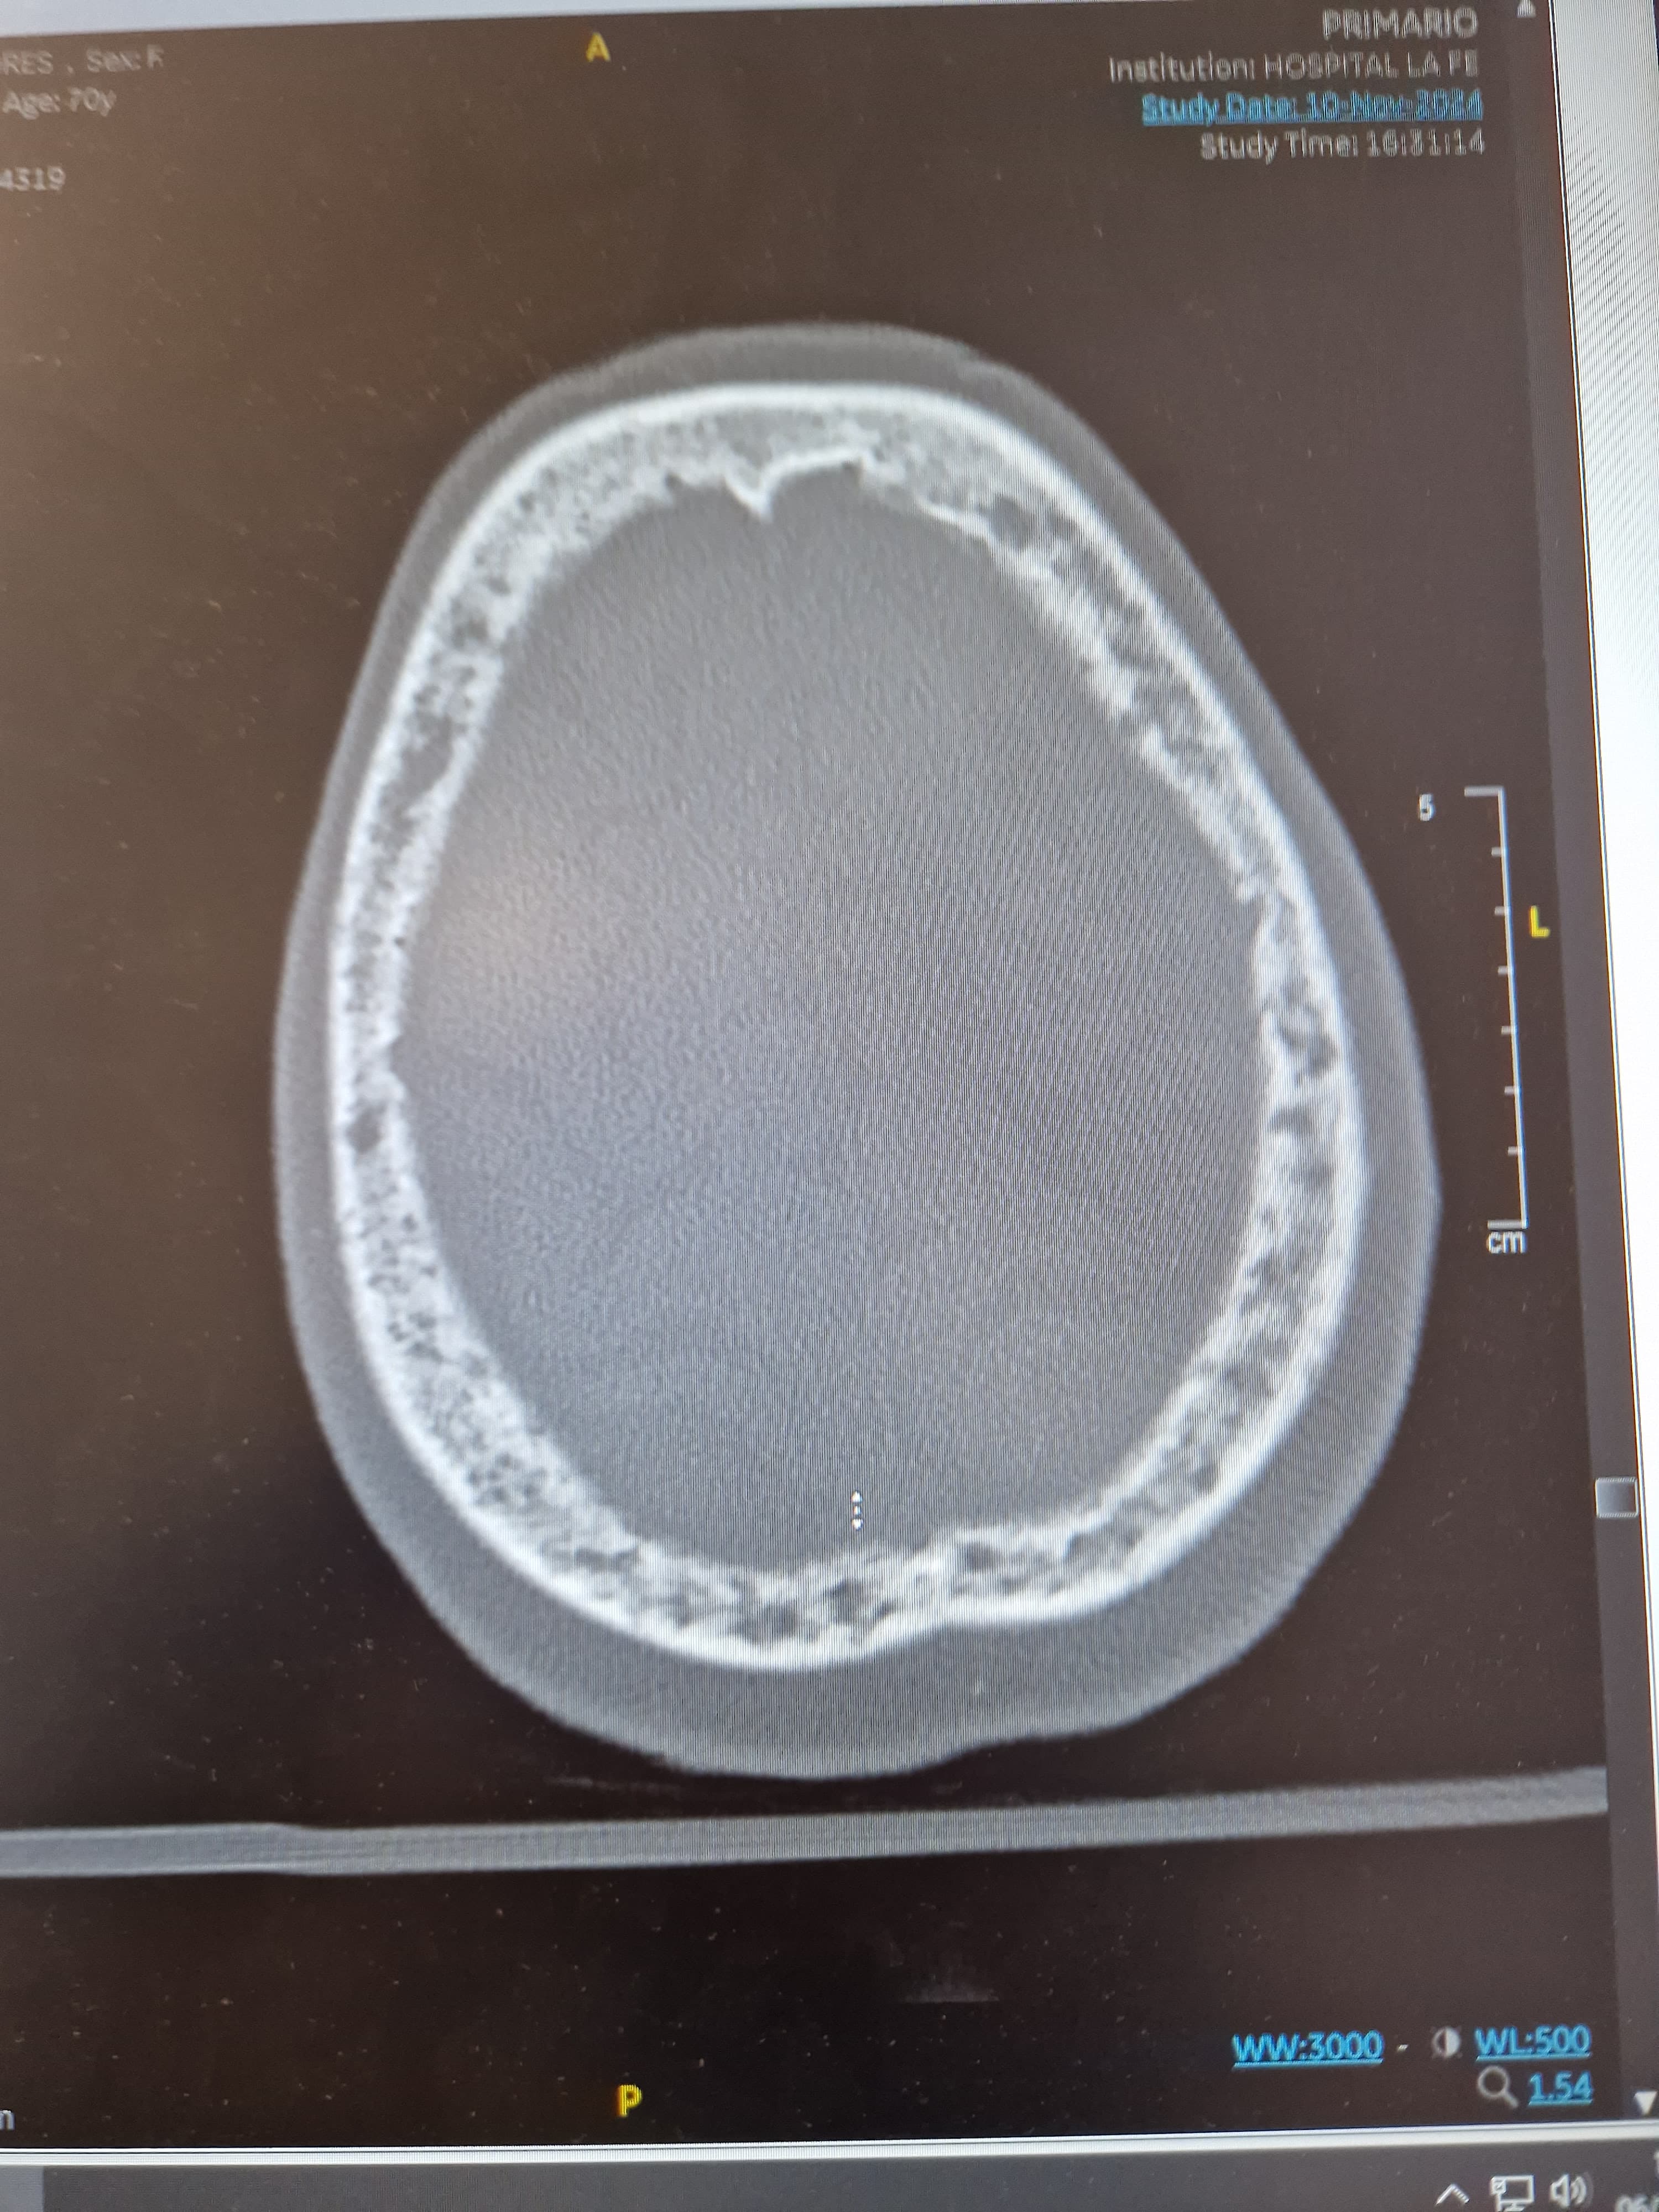

Tras realizar entrevista clínica a familiares destaca la rapidez de instauración de la clínica en menos de 24 horas, previamente la paciente se encontraba asintomática. Se decide realizar TAC para descartar lesiones cerebrales.